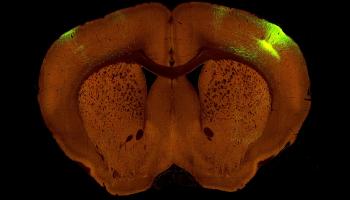

الدراسة وضعت الأساس للباحثين لفهم أفضل للكيفية التي تتواصل بها دوائر الدماغ في الأمراض والاضطرابات مثل مرض ألزهايمر والفصام